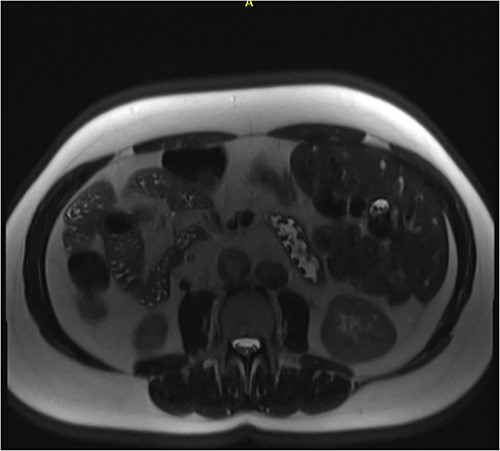

Following examination, a magnetic resonance cholangiopancreatography (MRCP) test was requested to exclude choledocholithiasis. 24 hours later, this confirmed gallstones, with 10 mm saccular dilatations near the hilar confluence (Figs 1 and 2). This dilatation was non-progressive according to previous scans, with unaffected pancreatic and intrahepatic ducts. Dilated portal vessels and varices were discovered to be directly communicating with the gallbladder fossa, suggestive of portal venous communication.

Coronal MRCP scan demonstrating a 10 mm area of saccular duct dilatation at the hilar confluence. Large, dilated vessels/varices surrounding the gallbladder fossa can also be appreciated.